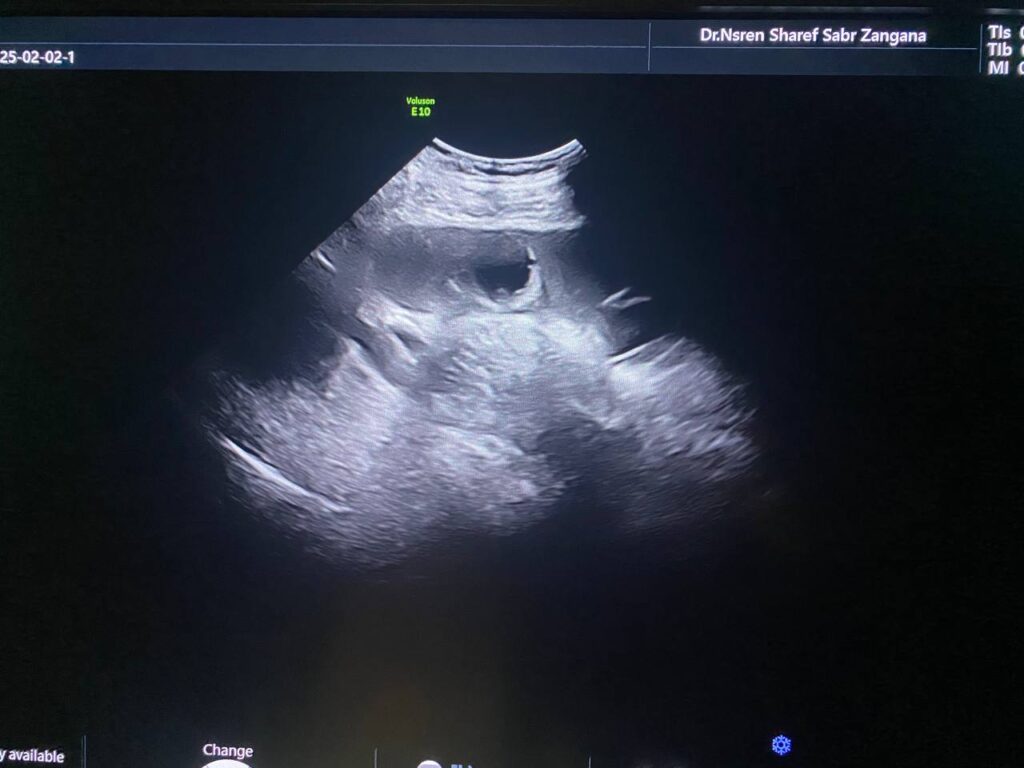

Right ovarian multilocular (>60 locules) solid mass , its size 170x140mm vascular on color doppler , color score 3-4 , with indistinct margins , associated with ascites , contains fine echoes , picture mostly of primary ovarian cancer ORADS 4 , no mass seen in the left ovary